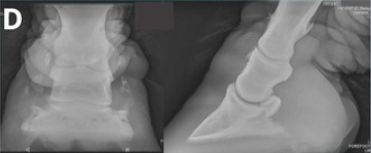

Image credit Oda Barhuf at Balanced Step.

Possibly a degree of P3 descent. Aged 19 here. CPL score D, exteme.